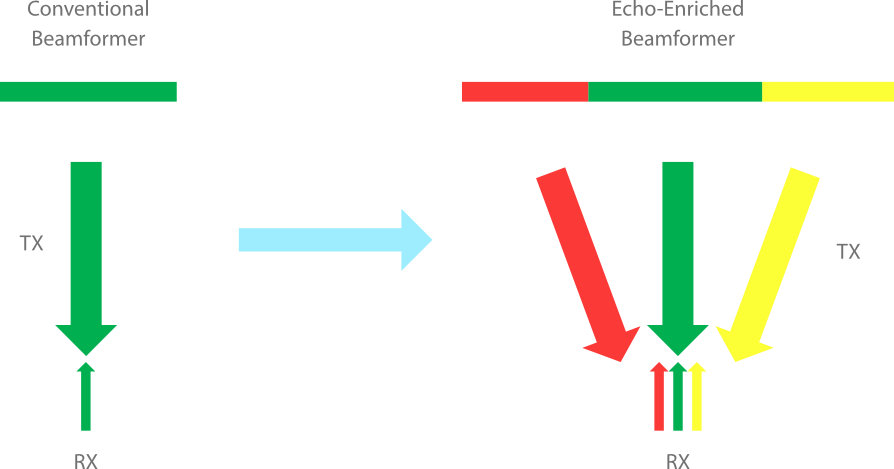

Forma??o de feixe enriquecido por eco

O formador de feixe enriquecido por eco permite o uso de sinais de eco tradicionalmente negligenciados de feixes adjacentes para formar um feixe de imagem mais fino e mais forte, proporcionando uma melhor resolu??o de imagem "fora de foco" e uma penetra??o mais profunda de imagem.